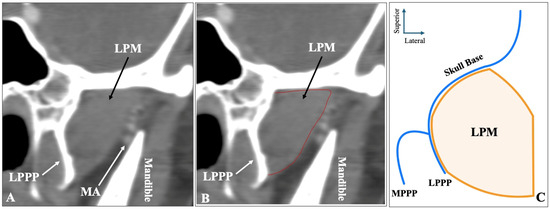

The third most common morphology was the one-headed configuration (no difference between superior-inferior) recorded in sagittal slices, observed in 54 sides (10.8%) (Figure 3). Out of 54 sides with one-headed LPM, 42 sides (77.8%) had the MA lateral, 12 sides (22.2%) had the artery medial to the muscle, and zero patients had the artery through the muscle on this type.

Figure 3.

The one-headed configuration of the lateral pterygoid muscle (LPM) recorded in sagittal CTA slices (A,B) and in schematic representation (C). LPPP = lateral pterygoid process plate.